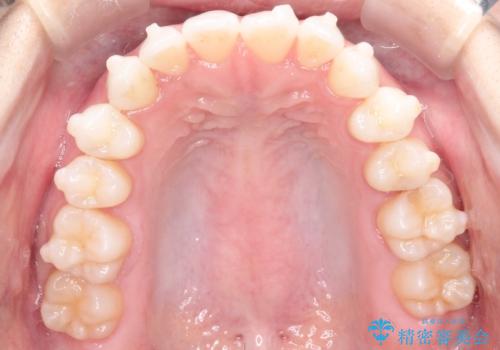

【インビザライン】前歯の凸凹をマウスピース矯正でなおしたい

- 前歯の凸凹を主訴に来院されました。

上の前歯は翼状捻転と呼ばれる状態でしたが、奥歯の遠心移動を行うことで配列スペースを確保することで綺麗に歯を並べることができました、

途中でインビザラインの使用時間が短くなってしまったため期間が予定より少し伸びましたが、1年半で満足いく結果となり患者様に喜んでいただけました。